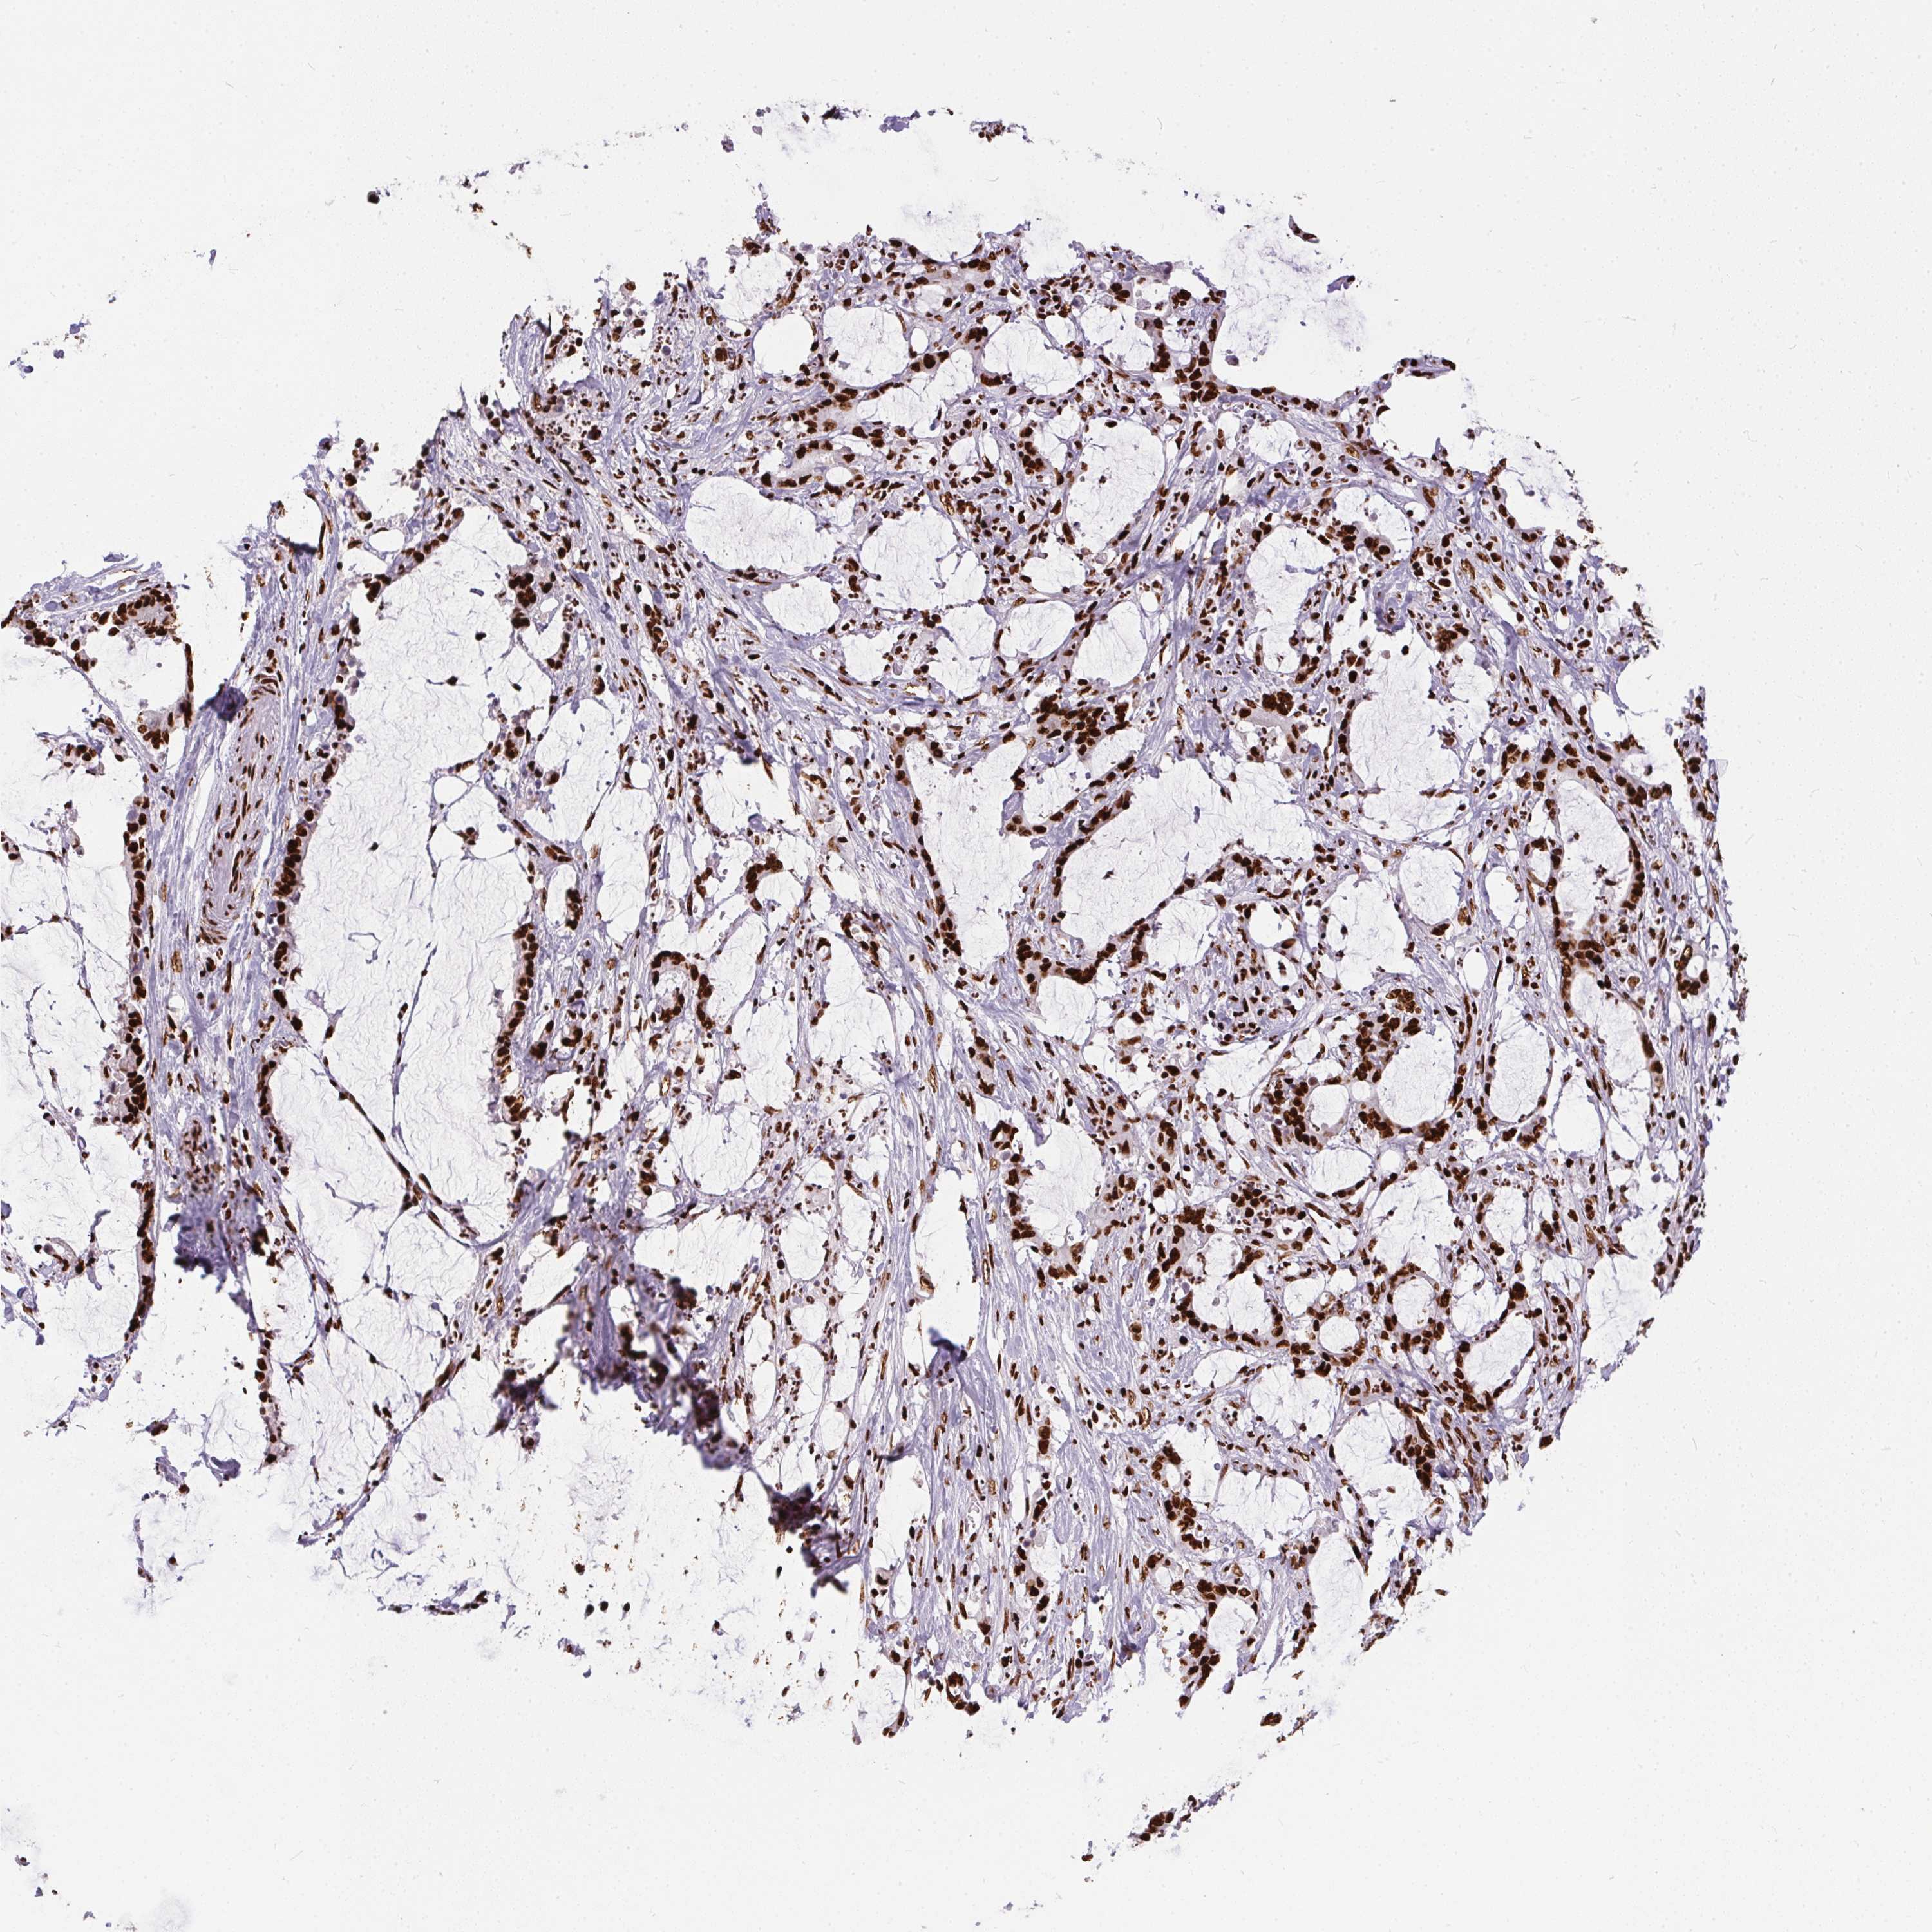

STOMACH CANCER - Protein expressioni

A mouse-over function shows sample information and annotation data. Click on an image to view it in a full screen mode. Samples can be filtered based on level of antibody staining by selecting one or several of the following categories: high, medium, low and not detected. The assay and annotation is described here.

Note that samples used for immunohistochemistry by the Human Protein Atlas do not correspond to samples in the TCGA dataset.

Antibody stainingi

Antibody staining in the annotated cell types in the current human tissue is reported as not detected, low, medium, or high, based on conventional immunohistochemistry profiling in selected tissues. This score is based on the combination of the staining intensity and fraction of stained cells.

Each image is clickable and will lead to virtual microscopy that enables deeper exploration of all samples and also displays staining intensity scores, fraction scores and subcellular localization as well as patient and tissue information for each sample.

Antibody HPA062248

Staining

High

Medium

Low

Not detected

Intensity

Strong

Moderate

Weak

Negative

Quantity

>75%

75%-25%

<25%

None

Location

Nuclear

Cytoplasmic/membranous

Cytoplasmic/membranous,nuclear

Adenocarcinoma, NOS